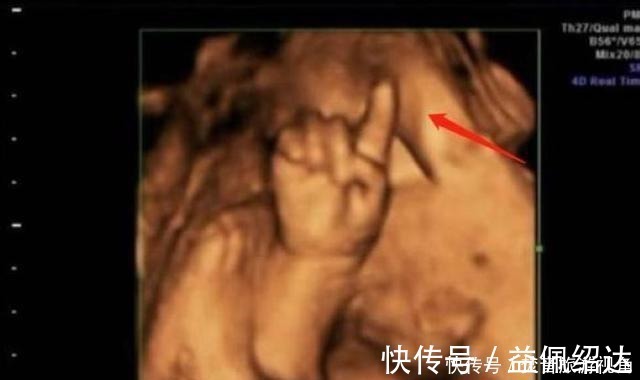

第一次做检查时,胎儿的脸部、身体都看得非常的清楚,让陈女士感到了很大的安慰。值得一提的是,孩子的一只手伸出了一个手指,非常的可爱。让人没想到的是,第二次检查时,孩子的手指伸出了两根,第三次手指变为了三根,最后一次检查,孩子的手指就变成了四根。

医生看到这种情况,也是非常的吃惊,他还调侃道:这孩子可是北大清华的料,可不能耽误人家,陈女士听后非常的开心。就这样,\\\"天才胎儿\\\"在网上迅速火了起来,他在子宫中掰手指算数成为了网友们新奇的谈资。